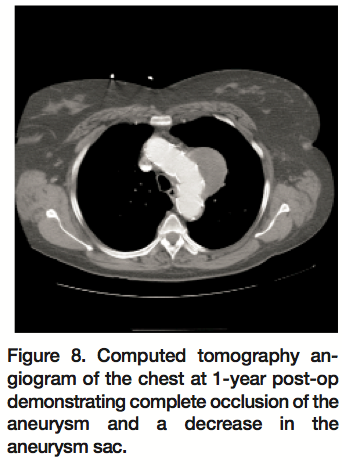

The patient is currently 1 year out from her surgery and is alive and well with no reported musculoskeletal weakness. She had a 1-year follow-up computed tomography angiogram of her chest, which showed the aortic arch aneurysm sac to still be completely excluded by the graft and a decrease in size of the aortic arch aneurysm from 7.4 x 6.7 cm to 6.4 x 5.6 cm (Figure 8). The second saccular aneurysm that was in the mid thoracic aorta is no longer seen.